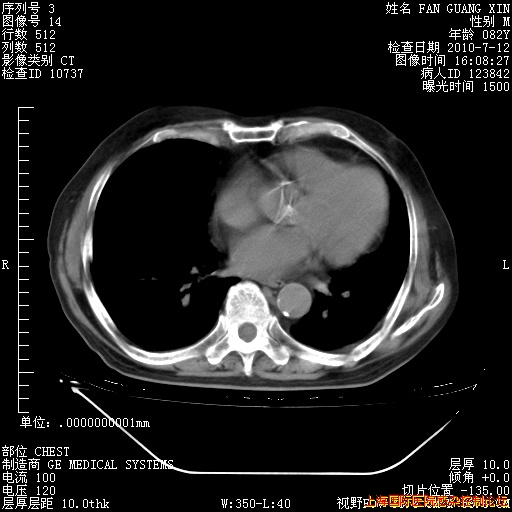

今天复查CT

今天CT

整整相隔30天的肺部CT好像有所好转啊。甲强龙减量第3天,需要观察体温。

海管,自昨日你和我通完话后,不知您岳父消化道症状有无缓解?体温怎样?阅读7.12日胸部ct,个人认为目前激素治疗是有效的,甲强龙减量是适宜的。因在抗痨治疗,需密切观察肝功、肾功能和血常规。不过,老年、长期住院和大量使用激素,很担心菌群失调发生